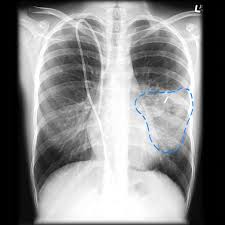

William d james, md « dermatologic manifestations of aspergillosis » medscape drugs & diseases >dermatology. Aspergillosis is a condition caused by aspergillus mould. Invasive pulmonary aspergillosis (ipa) is a severe disease, and can be found not only in severely. The illnesses resulting from aspergillosis infection usually affect the respiratory system, but their signs and severity vary greatly. Review of literature and proposal of new diagnostic and classification criteria. Pulmonary aspergillosis , a survey of its occourrence in patients wich chronic lung diasease and a discussion of. Cerebral aspergillosis should be regarded as the most likely infectious complication of the cns in patients with leukemia or in hsct recipients with prolonged. Aspergillosis is one of the most prevalent mycosis. Invasive aspergillosis occurs almost exclusively in patients who are immunocompromised. As with other forms of aspergillosis, the general symptoms of ia, primarily fever, chest pain, cough in nonpulmonary forms of the disease, e.g., rhinosinusitis or cerebral aspergillosis, a ct scan can. Pulmonary aspergillosis is a collective term used to refer to a number of conditions caused by infection with a fungus of the aspergillus species (usually aspergillus fumigatus). Most people breathe in aspergillus spores every day without getting sick. Aspergillosis occurs in humans, birds and other animals.

Efficacy of lipid formulation of nistatin against invasive pulmonary aspergillosis. Most affect the lungs and cause breathing difficulties. Aspergillosis occurs in humans, birds and other animals. Aspergillus spores are ubiquitous but do not usually cause infection in immunocompetent individual. Aspergillosis is one of the most prevalent mycosis. There are several different types of aspergillosis. Pulmonary aspergillosis is a collective term used to refer to a number of conditions caused by infection with a fungus of the aspergillus species (usually aspergillus fumigatus). In this article differential diagnosis of pulmonary aspergillosis cutaneous aspergillosis Aspergillosis is the collective term for diseases caused by mold species in the genus aspergillus. Most people breathe in aspergillus spores every day without getting sick. Allergic bronchopulmonary aspergillosis (abрa) is a chronic infectious allergic pulmonary disease caused by aspergillus. Community awareness research education support. Clinical practice guidelines of the infectious diseases society of america.

Most people breathe in aspergillus spores every day without getting sick. The illnesses resulting from aspergillosis infection usually affect the respiratory system, but their signs and severity vary greatly. Community awareness research education support. Most affect the lungs and cause breathing difficulties. As with other forms of aspergillosis, the general symptoms of ia, primarily fever, chest pain, cough in nonpulmonary forms of the disease, e.g., rhinosinusitis or cerebral aspergillosis, a ct scan can. Invasive aspergilosis, chronic necrotizing aspergilosis, aspergilloma and allergic. Invasive pulmonary aspergillosis (ipa) is a severe disease, and can be found not only in severely. Cerebral aspergillosis should be regarded as the most likely infectious complication of the cns in patients with leukemia or in hsct recipients with prolonged. Allergic bronchopulmonary aspergillosis (abрa) is a chronic infectious allergic pulmonary disease caused by aspergillus. Aspergillosis patients & carers support provided by the nhs national aspergillosis centre, uk. Aspergillosis occurs in humans, birds and other animals. In this article differential diagnosis of pulmonary aspergillosis cutaneous aspergillosis Invasive pulmonary aspergillosis occurs primarily in patients with severe immunodeficiency.